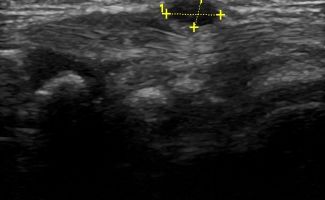

Soft Tissue Pathologies

- Lipomas

- Ganglia

- Tumors

- Foreign Bodies (glass and wood)